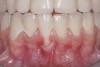

Fig 3. Two-year follow-up of same patient shows spontaneous root coverage.

Figure 3

When the tooth is properly aligned within the arch, treatment is managed with reference to Miller’s classification.7 Because most post-orthodontic GR cases are classified as Miller Class I and II defects, the authors focus on the management of these two classes only, and within the scope of this article, Miller Class III and IV defects are not addressed. Surgical root coverage of both Miller Class I and II defects is one treatment choice. However, in Miller Class I cases, a conservative approach can be considered, as well. Such an approach consists of supportive periodontal treatment (SPT)—professional periodic deposit removal every 2 to 3 months during a 1- to 2-year period. The authors’ clinical experience shows that spontaneous root coverage may occur following this conservative approach, particularly in young patients (Figure 2 and Figure 3). Similar results have been reported in a 3-year prospective study in which recession defects healed spontaneously following improvement in oral hygiene standards in children.30 In cases in which no root coverage is observed at the end of the follow-up period, surgical root coverage can be considered.